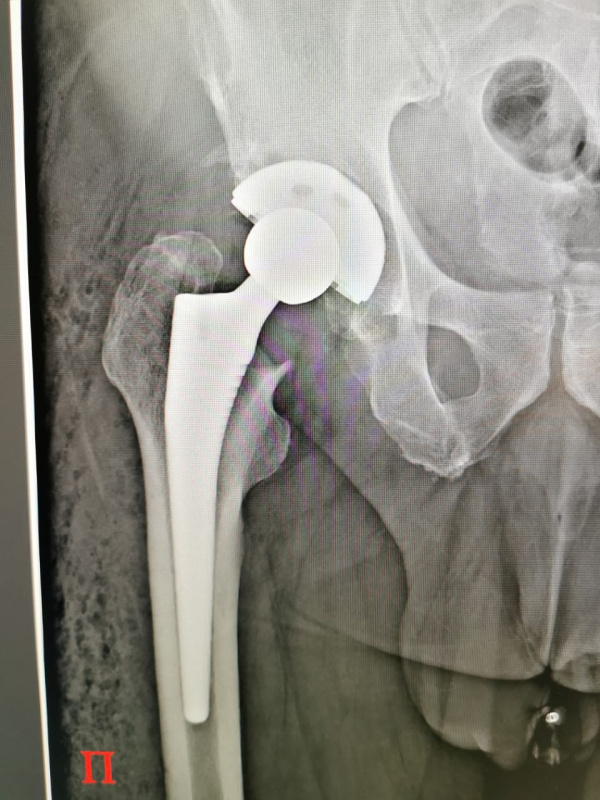

- Протезирование коленного и тазобедренного суставов. Они выполняются по квоте: коленные - по федеральной, тазобедренные - по региональной. Также востребованы артроскопические операции на плечевом суставе по федеральной квоте, восстановление связок на коленном суставе; операции на стопах - по федеральной и региональной квотам. С начала года мы провели 126 операций по протезированию тазобедренного сустава, 94 - коленного, 222 артроскопических операции

Пациент несколько дней проводит в хирургическом отделении, затем 10 дней в отделении реабилитации. Полтора месяца ходит на костылях, еще полтора с тросточкой - и все. За 4-5 месяцев подвижность, как правило, восстанавливается полностью. Через 7-8 месяцев уже можно ставить второй сустав - при необходимости.

Если пациент возрастной, то в первый послеоперационный день он садится, опускает ноги, и, если голова не кружится, то назавтра начинает ходить. Молодые пациенты встают на костыли в первый день. Это касается как операций на тазобедренных, так и на коленных суставах. Тут как раз главная задача - ранняя активация, чтобы пациенты скорее начали двигаться - это сокращает восстановительный период. Чем быстрее начнете двигаться, тем меньше осложнений со стороны легких, системы кровообращения. Естественно, нагрузка нужна дозированная, и, конечно, все индивидуально: есть более сложные операции, есть менее.

-От наличия сопутствующих заболеваний, о чем мы уже сказали, и от качества импланта. Мы ставим протезы американского производства. Мы умеем с ними работать, они прекрасно себя показали на практике. Под санкции они не попали, разве что усложнилась логистическая цепочка, так что поставки идут, может быть, не так быстро, как нам хотелось бы. Но мы работаем без простоя. Проблема была, когда ввели санкции на высокомолекулярный полиэтилен, который уменьшает трение между компонентами протезов, предупреждая их изнашиваемость, но сейчас, насколько я знаю, мы не испытываем сложностей с его закупкой.

-Конечно. И самый хороший результат показывает операция на тазобедренном суставе.